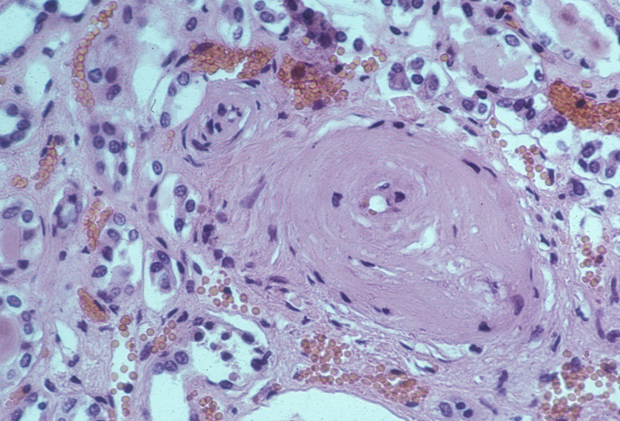

MBBS Medicine (Humanity First): Hyaline Arteriolosclerosis

Tulang rawan hialin sederhana dalam struktur, tanpa saraf atau pembuluh darah. For faster navigation, this Iframe is preloading the Wikiwand page for Hialin. care are aspectul, transparența sticlei. țesut hialin. Hialin memiliki arti transparan atau tidak berwarna.